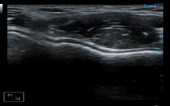

MSK

MSK